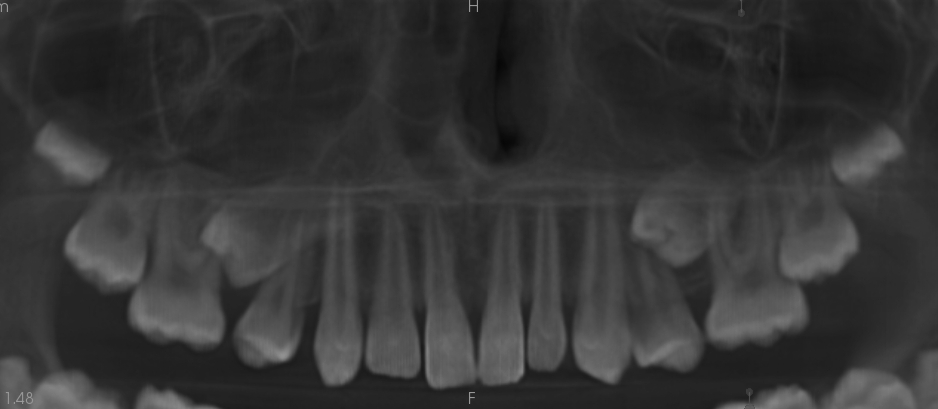

Resorpcja zęba to proces powstania ubytku twardych struktur zęba wywołanego przez osteoklasty bez kontaktu ze środowiskiem jamy ustnej, między innymi na skutek ucisku wywieranego przez ząb zatrzymany. Dla lekarza ortodonty jest istotne ustalenie, czy zęby zatrzymane lub twory nadliczbowe powodują resorpcję zębów stojących w łuku w celu wczesnej eliminacji przyczyny resorpcji. Celem pracy jest przedstawienie opisu przypadku zastosowania tomografii stożkowej w diagnostyce nieprawidłowo położonych zawiązków zębów przedtrzonowych drugich górnych. Stwierdzono, że tomografia stożkowa jest skuteczną metodą oceny wczesnej resorpcji zewnętrznej korzeni zębów.

Tooth resorption is the process of appearing of a defect of hard tissues of teeth caused by osteoclasts not having contact with oral cavity environment, eg. due to mechanical pressure exerted by an impacted tooth. It is essential for an orthodontist whether impacted teeth or supplementary teeth cause resorption of erupted teeth in order to early eliminate the causative factor of the resorption. The aim of the paper is to describe a case report of cone-beam computed tomography (CBCT) in diagnostics of incorrectly located germs of upper second premolars. It was found that CBCT was an efficient method of imaging of early external root resorption.